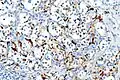

Micrograph of a carotid body tumour (a type of paraganglioma).

Micrograph of a carotid body tumor with the characteristic Zellballen. H&E stain.

The paragangliomas appear grossly as sharply circumscribed polypoid masses and they have a firm to rubbery consistency. They are highly vascular tumors and may have a deep red color.

On microscopic inspection, the tumor cells are readily recognized. Individual tumor cells are polygonal to oval and are arranged in distinctive cell balls, called Zellballen.[10] These cell balls are separated by fibrovascular stroma and surrounded by sustentacular cells.

With immunohistochemistry, the chief cells located in the cell balls are positive for chromogranin, synaptophysin, neuron specific enolase, serotonin, neurofilament and Neural cell adhesion molecule; they are S-100 protein negative. The sustentacular cells are S-100 positive and focally positive for glial fibrillary acidic protein. By histochemistry, the paraganglioma cells are argyrophilic, periodic acid Schiff negative, mucicarmine negative, and argentaffin negative.